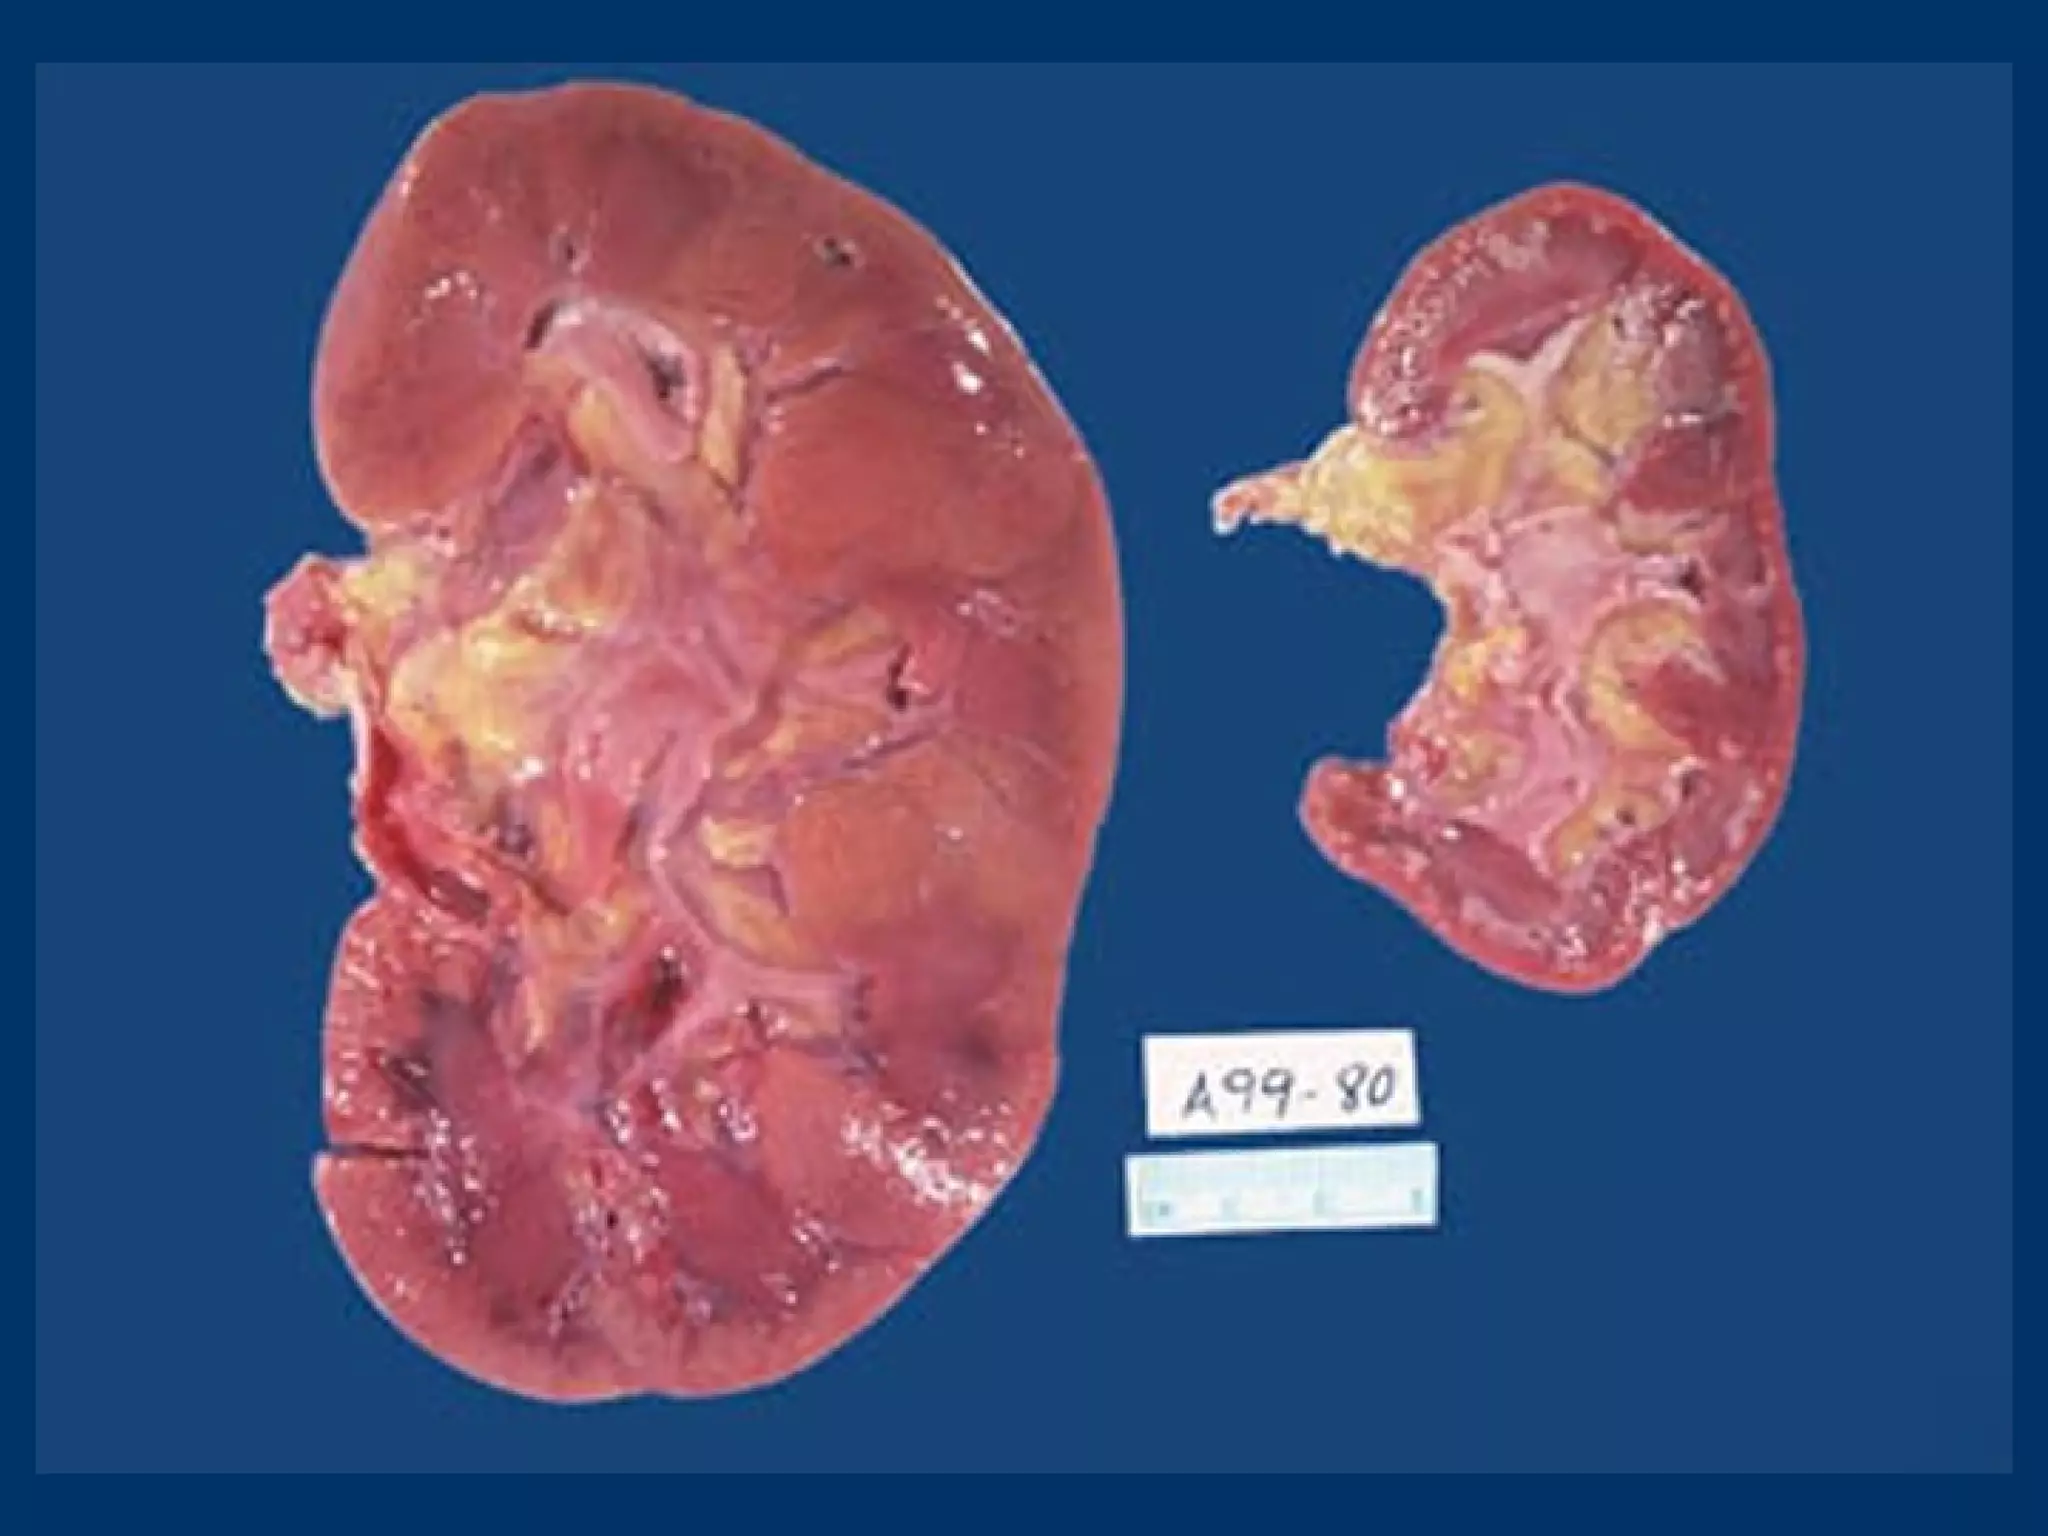

• #9 Kidney: atrophy via renal artery stenosis. NB: decrease in cortex (most metabolically active cells)